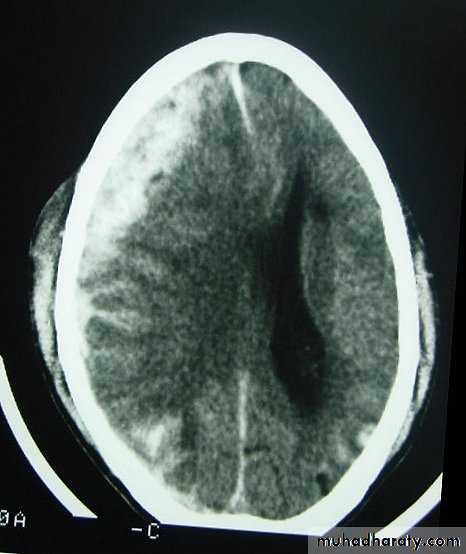

Chronic Subdural Haematoma

Most common in infants and in adults over 60 years of age secondary to SLIGHT blow to the head which may pass unnoticed.

Source of bleeding (haematoma): usually from bridging veins as they pass to the venous sinuses.

The patients present with progressive neurological deficits more than 3 weeks after the trauma.

The initial head injury is often completely forgotten.

CT scan: the acute clotted blood is initially appears white (hyperdence), but as it liquefies, it slowly becomes black (hypodense).

They should be drained if they continue to enlarge.

They are evacuated by drilling burrholes over the collection and washing it out with warmed saline.